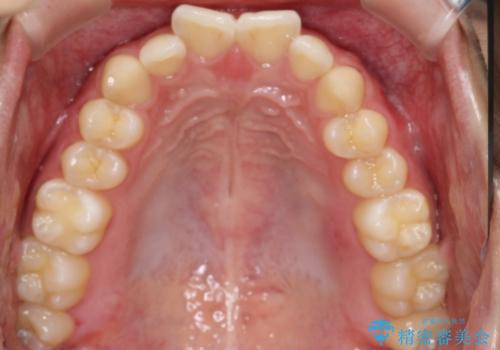

マウスピース矯正で前歯のガタツキを改善! 短期間で治療完了

- 前歯のガタツキが気になるとのことで来院されました。

マウスピース矯正で治療することとしました。